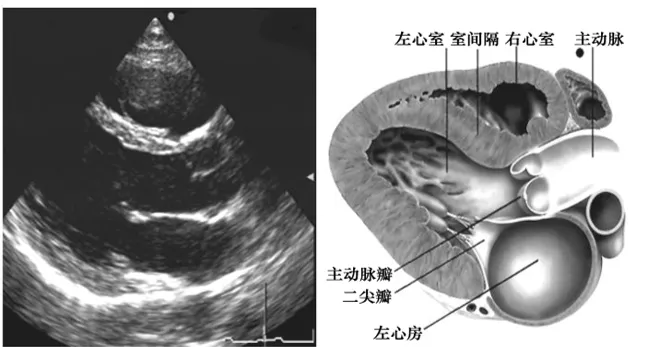

胸骨旁左室长轴切面

探头位置:探头置于胸骨左缘3、4肋间,检查声束平面与右锁骨关节和左乳头连线平行。

观察内容:

● 腔室大小:右室,左房,左室,主动脉根部及升主 动脉近端。

● 室壁厚度:前室间隔和左室后壁。

● 瓣膜活动:二尖瓣,主动脉瓣(右冠状动脉瓣和无冠状动脉瓣)。

● 室壁运动: (前室间隔和左室后壁)。

● 心功能测定